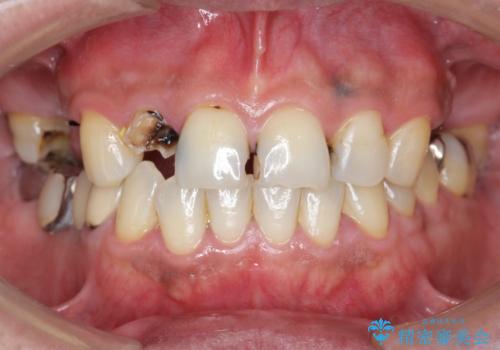

かぶせものと歯ぐきの境目が黒い 40代女性

保険のかぶせ物・詰め物を金属を使わないセラミックへ 自然な見た目へ